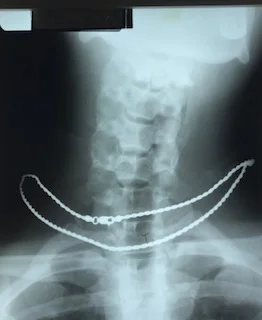

Before Corrective Care (manual short term adjusting)

After Corrective Care (manual short term adjusting)